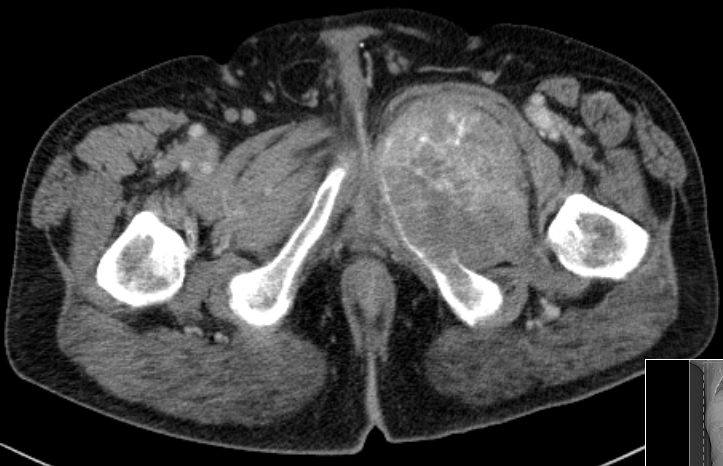

| Knochenmetastasen | 61-jähriger Patient, der vor 2,5 Jahren ein primär hepatisch metastasiertes Rektumkarzinom hatte.

9 Monate FOLFIRI/Erbitux ergaben eine CR der Lebermetastasen.

Mit verschiedenen systemischen und chirurgischen Maßnahmen Tumorkontrolle bis jetzt.

Nun Schmerzen in der linken Leiste besonders beim Treppensteigen.

Das CT zeigt eine Schambeinmetastase mit großem Weichteiltumor.![]() |

Der Weichteiltumor ragt nach caudal in den Adduktorenkanal.![]() |

Cranial ist das symphysennahe Schambein völlig zerstört.![]() |